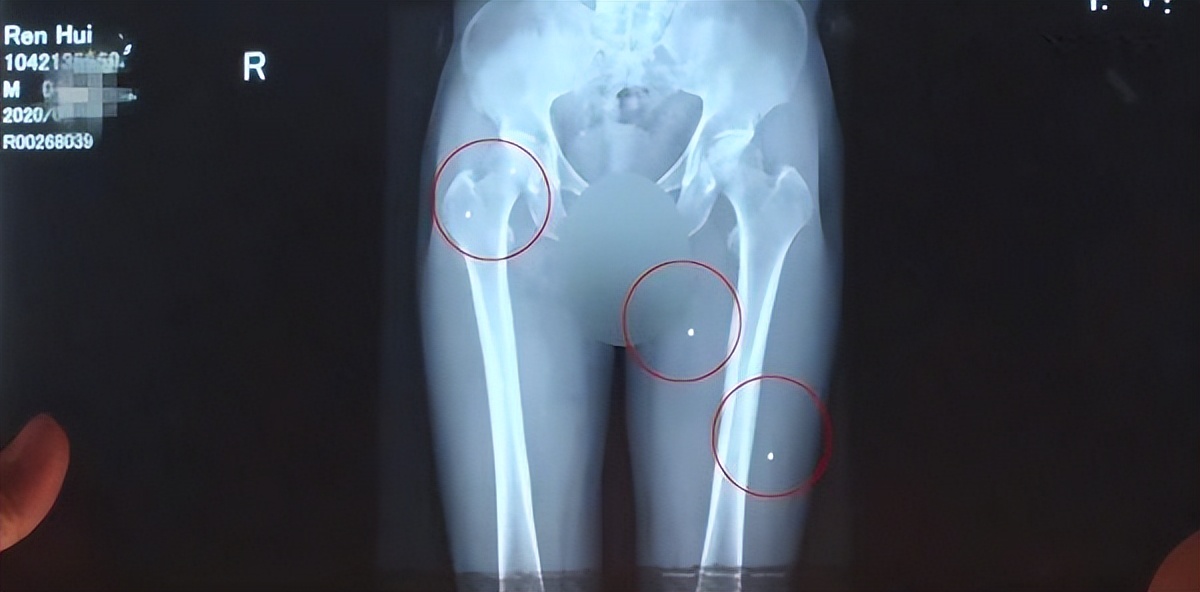

经过验伤,警方判断 这些伤口是用*弹霰**枪打出来的,虽然这种*弹霰**枪是土制的,用的也不是真的*弹子**,但威力依然很大。

因为发射出去的小弹丸很多,所以伤口也多,遍及全身。

医院给任辉取出来了一些,但有些因为太深,已经无法取出来,只能留在体内。

这次受伤,也是极其严重的,取不出的弹丸成了永久的后遗症,之后很长一段时间,任辉应该都不能正常走路了。